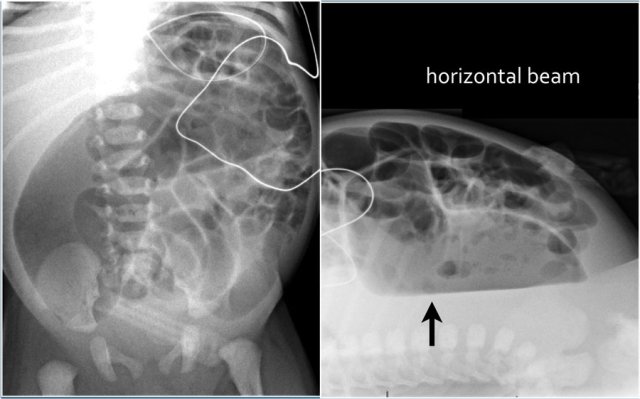

Massive dilatation is seen in complete obstruction and is accompanied by fluid levels on the dorsal decubitus radiograph.

On the left image the bowel is dilated and the diameter exceeds L2 interpedicular width in a patient with meconium ileus.

On the image on the right there is massive dilatation in a neonate with jejunal atresia.

A dorsal decubitus radiograph may help as colonic obstruction may produce long fluid levels.